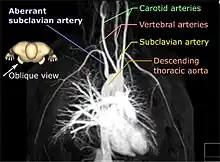

MRA has been successful in studying many arteries in the body, including cerebral and other vessels in the head and neck, the aorta and its major branches in the thorax and abdomen, the renal arteries, and the arteries in the lower limbs. For the coronary arteries, however, MRA has been less successful than CT angiography or invasive catheter angiography. Most often, the underlying disease is atherosclerosis, but medical conditions like aneurysms or abnormal vascular anatomy can also be diagnosed.